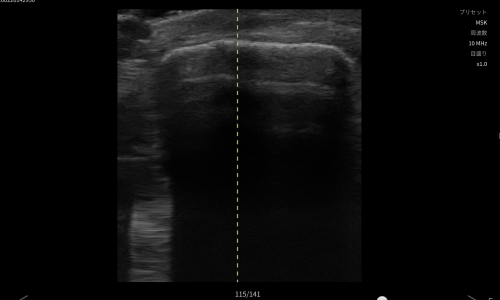

臨床的に高齢者の転倒による膝強打では膝蓋骨骨折を強く疑う所見。エコーで関節内血腫を確認し、膝蓋骨に骨折様所見を認め、膝蓋骨骨折および関節内損傷を疑い整形外科へ紹介しました。

関節穿刺にて血腫を確認後、MRIで膝蓋骨骨折を確認。縦方向に亀裂が入り2分割。その他の関節内骨折は認めず。